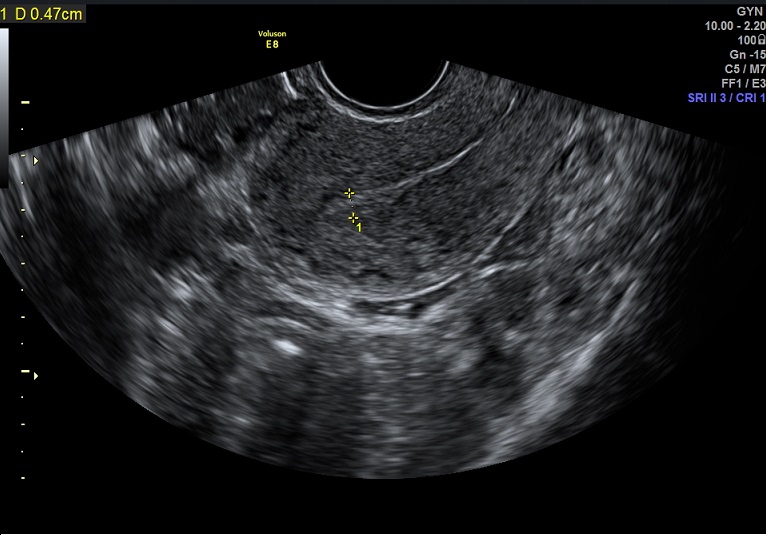

2015-3-19 月经第24天检查 内膜厚0.6cm 内膜血流:1级 内膜波动不明显 左卵巢黄体 子宫动脉: L:PSV:27.3cm/s EDV:4.7cm/s RI:0.83 S/D:5.8 PI:2.5 R: PSV:28.8cm/s EDV:2.0cm/s RI:0.93 S/D:14.4 PI:3.8 舒张早期血流缺失 检验: 2015-3-11 E2: 155.42 LH: 7.00 FSH: 4.43 P: 2.45 |

2015-3-19图示